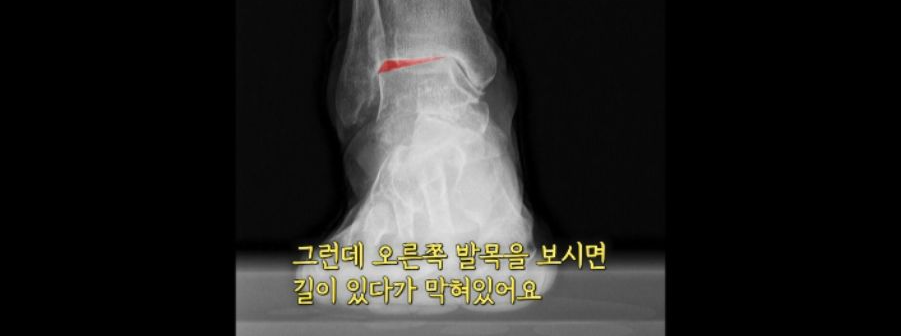

작은 구멍 두 개로 수술 끝? 발목인대접합(봉합)수술

전에는 발목을 확 열어서 인대접합수술을 했다. 요즘은 발목에 구멍을 내고 관절내시경을 넣어 보면서 한다.

인대가 파열될 때 나와 떠다니는 뼛조각들을 하나 하나 찾아 제거하고,

(중간중간에 엑스레이로 보면서 남은 뼛조각이 있는지 확인한다. 요즘 내시경수술/시술은 엑스레이 사진이나 영상을 활용하는 게 많네)

뼈에 구멍내 수술실달린 나사를 넣어 고정하고,

끊어진 인대를 장력을 실이 지지하는 형태로 연결해준다. 봉합.

발목연골은 위 그림에서 거골과 연골 사이에 있다. 그 화면은 그냥 지나가서 말로 설명.